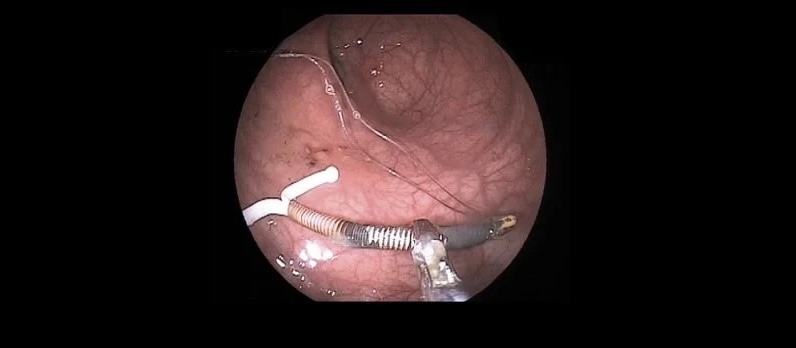

- Histeroscopía diagnóstica (método de elección)

La histeroscopía permite visualizar directamente la cavidad uterina y evaluar el grado de las adherencias.

Sí. El tratamiento es quirúrgico y mínimamente invasivo:

- 🔬 Histeroscopía quirúrgica, para liberar las adherencias

👉 En casos bien tratados, es posible recuperar la anatomía uterina y mejorar el pronóstico reproductivo.